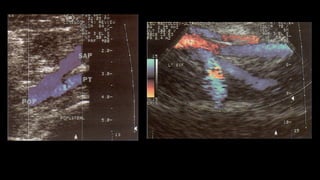

• Vena poplítea: vPosiciónposteromedial: vEje longitudinal de la VP, ascendiendo al canal aductor hasta la parte distal de la VFS. vSuperficial a la arteria poplítea. vContinuar distalmente hasta la bifurcación (troncos tibial posterior y peroneal). vEje transversal: comprobar compresibilidad.

üPara demostrar lapermeabilidad y competencia se realiza la maniobra de compresión externa, tiene alta sensibilidad y especificidad para detectar trombosis. De preferencia se realiza en un corte transversal del vaso para evitar desplazamiento. üPara demostrar competencia valvular se utiliza la maniobra de Valsalva a través de inspiración profunda y sostenida, el flujo al Doppler color debe de cesar

CRITERIOS  DIAGNÓSTICOS  DE  TVP 1. Visualización  directa  del  trombo  como  estructura  ecogénica en  la   luz  de  la  vena. 2. Medición  de  los  cambios  provocados  por  la  presencia  del  trombo   (distensión  pasiva  del  vaso,  pérdida  de  compresibilidad). 3. Detección  de  un  cambio  de  un  cambio  en  la  dinámica  del  flujo   venoso  (ausencia  total  o  flujo  alterado  alrededor  del  trombo).